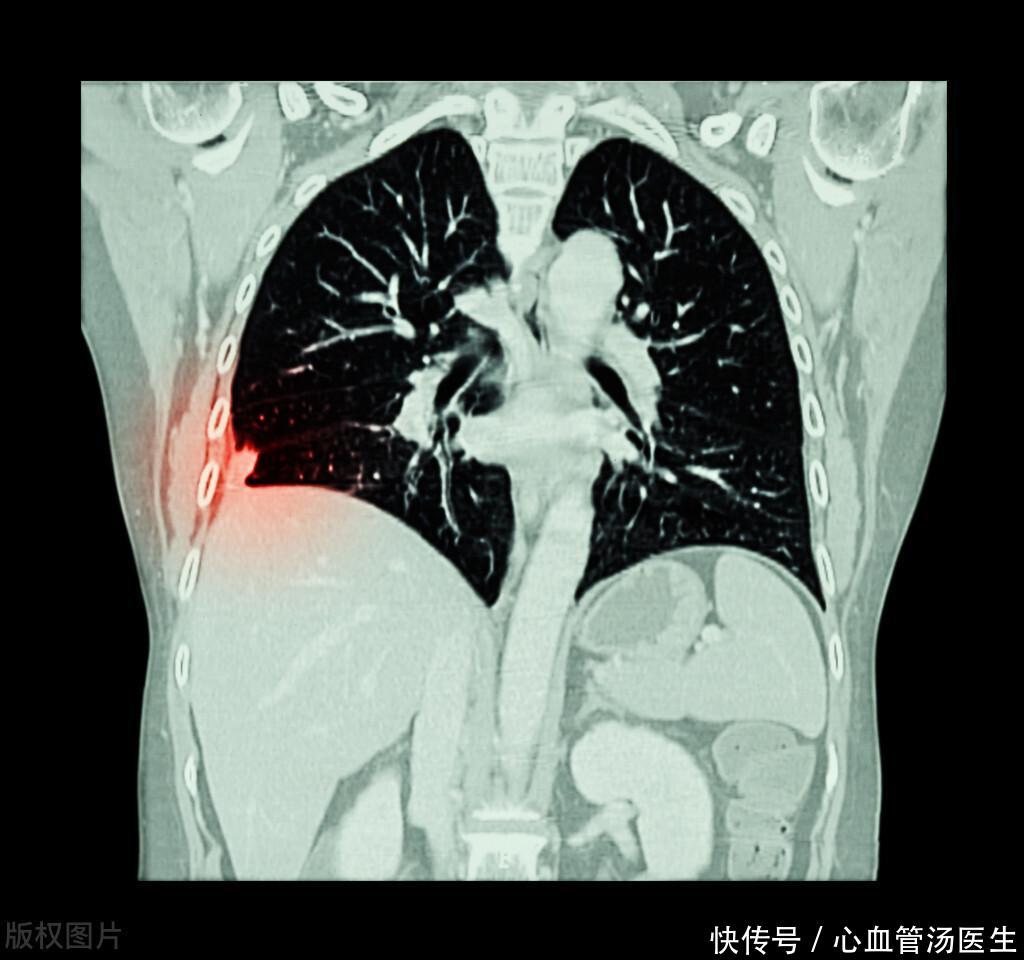

只是咳嗽1月,却查出肺癌晚期,如何早期发现肺癌?